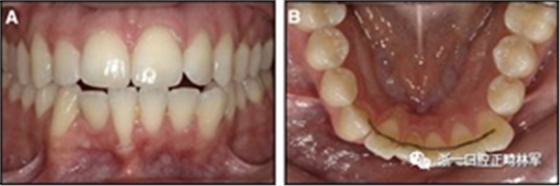

粘合保持器被移除,并放置固定裝置(圖15),僅限于患者要求的下頜弓。在第一階段牙周過(guò)程中,將結(jié)締組織移植物置于下頜右側(cè)中切牙的面?zhèn)取?個(gè)月后進(jìn)行第二階段牙周過(guò)程(圖16)。包括有意識(shí)的垂直骨質(zhì)評(píng)分以啟動(dòng)區(qū)域加速現(xiàn)象,以及顯著的面?zhèn)群蜕鄠?cè)植骨以糾正骨開(kāi)窗。

圖15.下頜右側(cè)中切牙區(qū)域軟組織移植前的初始排齊:A,正面視圖; B,咬合面視圖; C,軟組織移植2周后,初始牙周手術(shù)。